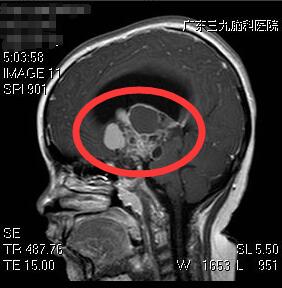

孩子术前颅内肿瘤

为进一步确诊,刘女士带着小敏前往广东三九脑科医院就医。据该院副院长、神经外五科主任鲁明介绍,患者体形肥胖,有68斤,身高偏矮,只有121厘米,头颅磁共振检查提示鞍区占位性病变,结合其他临床症状及相关检查,考虑为颅咽管瘤可能性大。

5月22日,鲁明主任为患者在全麻下行巨大颅咽管瘤切除术。因肿瘤巨大,约5cm×5.6cm×7.7cm厘米,包裹了颈内动脉、大脑前动脉和中动脉,且肿瘤位于脑深部,钙化明显,质地坚韧,故手术难度极大。经过近12个小时的挑战,肿瘤被顺利切除。目前,小敏康复良好。